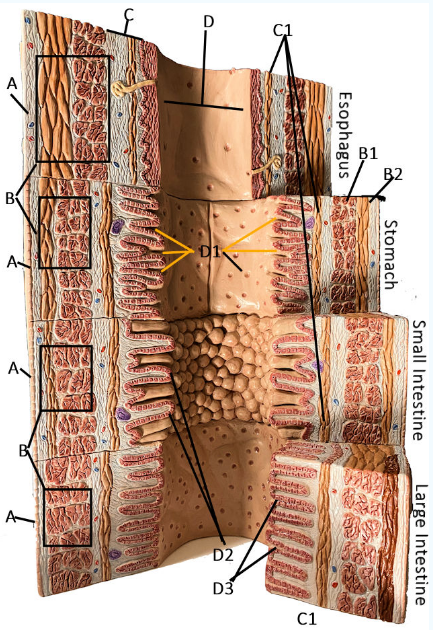

GI Cytology

A

Serosa

B Esophagus

Muscularis externa: skeletal, skeletal/smooth, and smooth, circular and longitudinal

B Stomach

Oblique, circular, and longitudinal smooth muscle

B Small intestine

circular and longitudinal smooth muscle

B large intestine

circular and longitudinal smooth muscle

C

Submucosa: areolar and dense connective tissue

D

Lumen

D1

Gastric glands/pits

D2

Villi of small intestine

D3

Intestinal crypts of large intestine